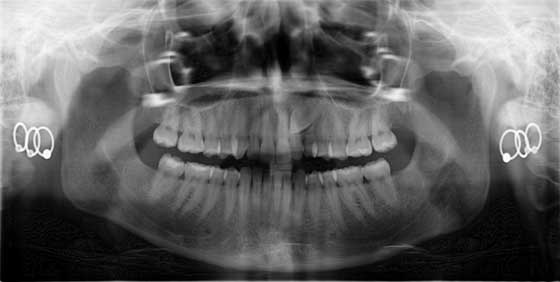

Patients who present with impacted maxillary canines offer unique and oftentimes challenging restorative needs. There is much to consider with the diagnosis, comprehensive treatment planning, and execution of bringing these teeth into the arch. The skills of an orthodontist, oral surgeon/periodontist, and general dentist are all needed to bring about a successful outcome. Dr. Stacey Simmons presents such a case showing how regardless of the potential obstacles and the extended duration of treatment, proper planning can facilitate an ideal result. Click here to read more.